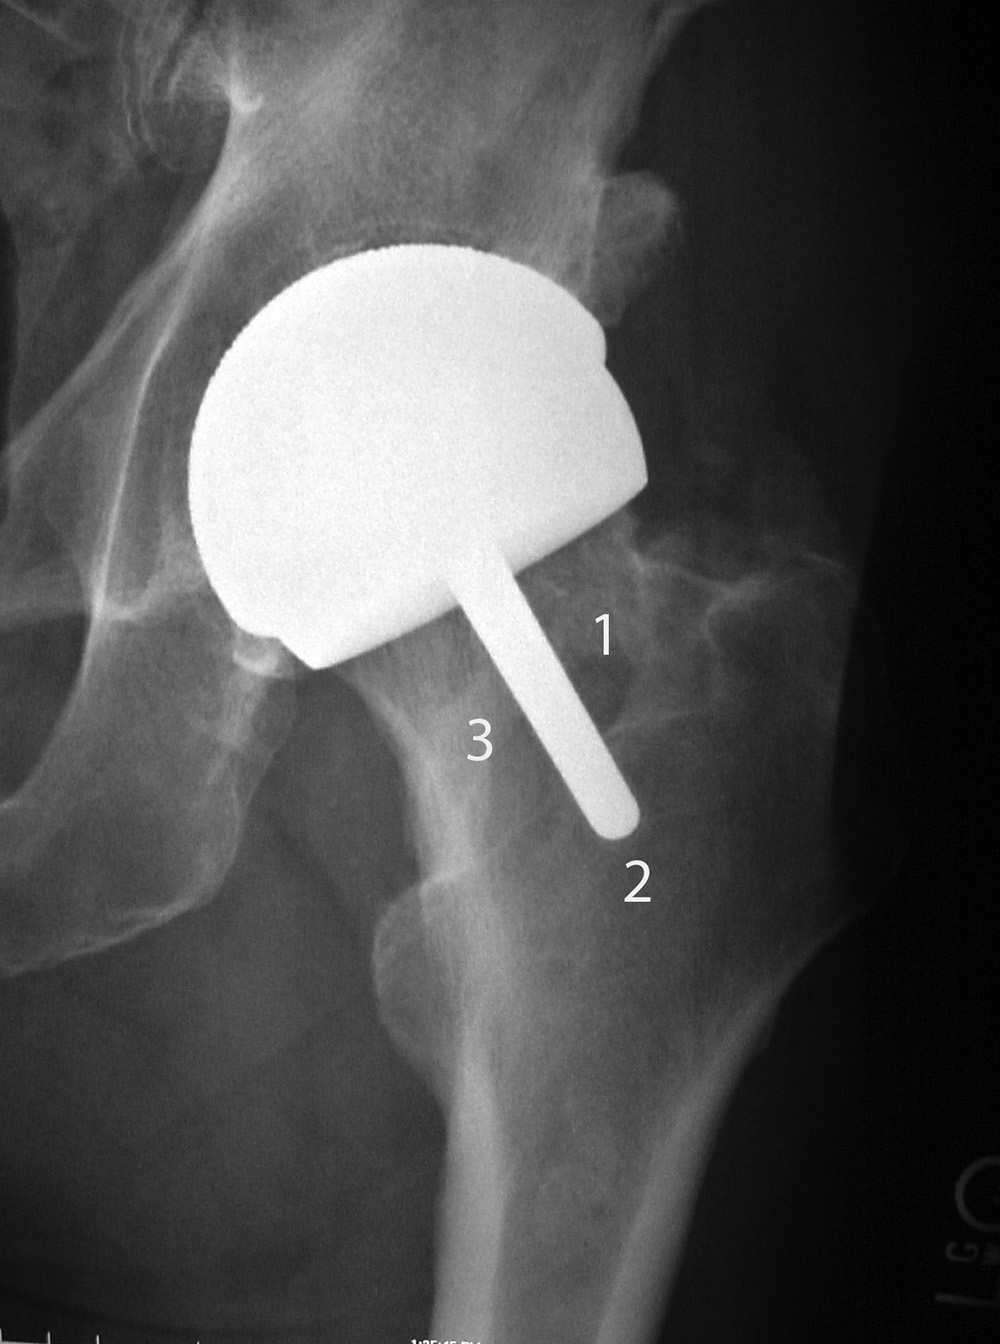

| Bipolar hemiarthroplasty (prosthesis) |

Bipolar hemiarthroplasty (prosthesis) |

Bipolar hemiarthroplasty (prosthesis)

| A free riding acetabular cup is press fit into the native acetabulum. The acetabular cup articulates with a prosthetic femoral head and stem component. From Benjamin, 1994 |

From Benjamin, 1994 |

92 year-old woman treated for left femoral neck fracture. From Taljanovic, 2005 |

There are three basic types of hip arthroplasty. Partial hip replacement or hip hemiarthroplasty replaces the femoral head and neck and leaves intact the native acetabulum. Hip hemiarthroplasty may consist of a single metallic unit, a unipolar hemiarthroplasty or endoprosthesis (figure: hip endoprosthesis). Or it may consist of a bipolar hip hemiarthroplasty in which there is replacement of the femoral head and neck and placement of a prosthetic acetabulum which is press fit into the native acetabulum. The bipolar hip prosthesis acetabulum is a polyethylene lined metal cup. It fits into a small femoral head which is locked to the attached metal femoral stem (Mulcahy, 2012). The bipolar hip hemiarthroplasty allows motion between the prosthetic femoral head and the polyethylene lined cup as well as between the cup and the native acetabulum (figure: bipolar hip prosthesis).